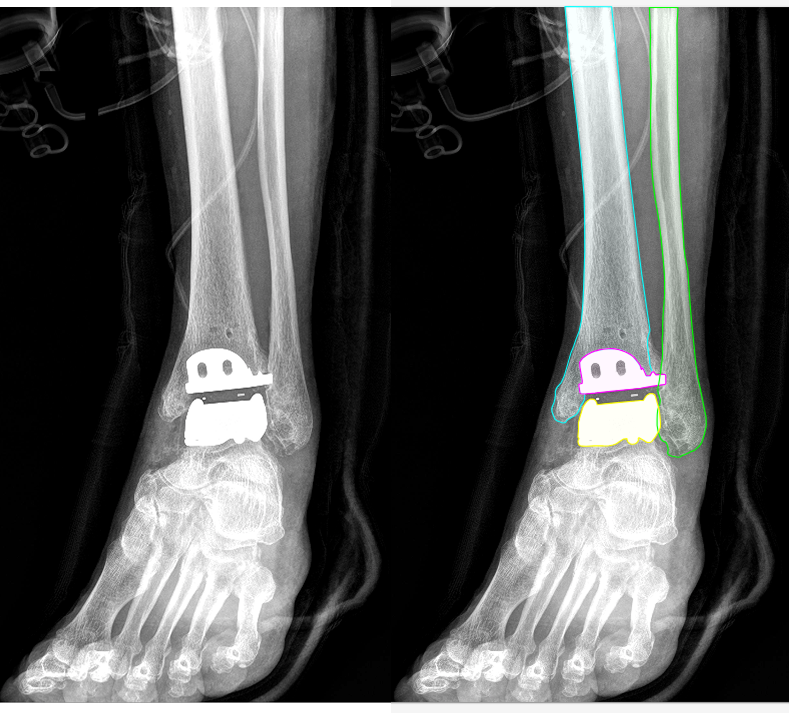

발목(Ankle): 경골, 비골, 거골에 대한 세그멘테이션 및 경골 바깥쪽 끝에 대한 키포인트를 지정했습니다.